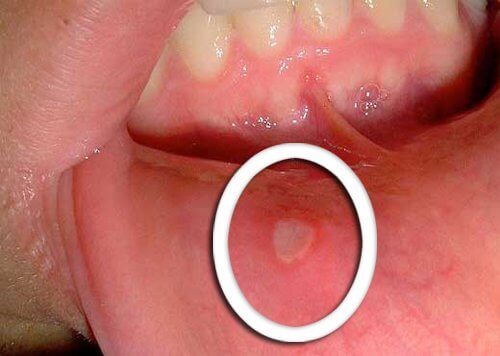

- Det tidligste symptomet på munnsvelgkreft er små sår som ikke leges.

- Det er typisk at røde eller hvite områder vises på tungen, tannkjøttet eller på leppene.

- Vær oppmerksom på eventuelle uvanlige endringer som ikke blir bedre i løpet av få dager; da må du oppsøke lege.